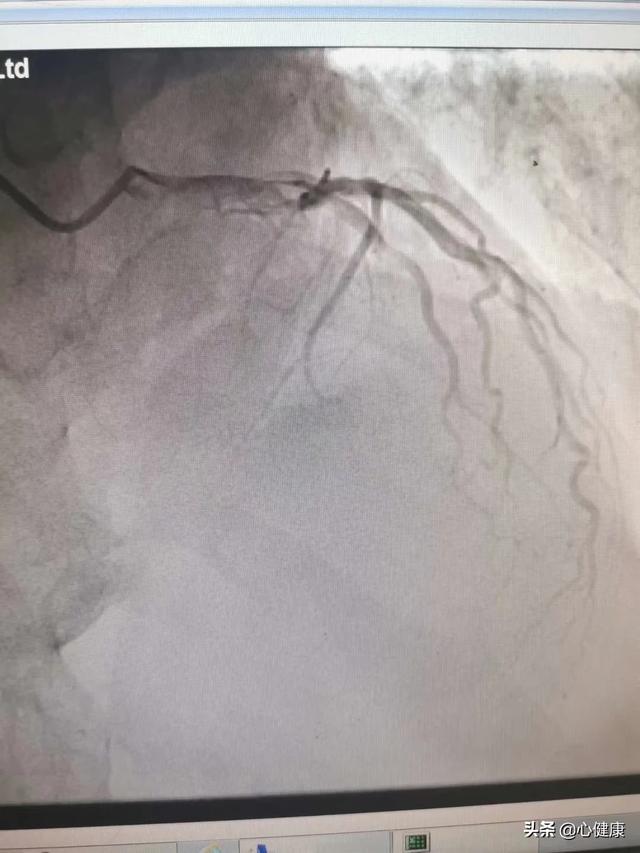

心脏造影,准确的来说是冠脉造影,这只是一个检查,来了解心脏表面的给心脏供应血液的血管(冠状动脉)壁上是否存在动脉粥样硬化斑块?如果有,造成血管腔的狭窄程度又如何,从而判断是否患有冠心病,这也是诊断冠心病的金标准。

心脏造影是心血管的常见检查,是诊断和治疗冠心病的一种常见方法,在一定程度上说,心脏造影是诊断冠心病的“金标准”;也就是说有没有冠心病,有没有心血管狭窄,做个造影就知道了!

冠脉造影是什么?

冠脉造影是冠心病确诊的金标准,更是一种侵入性检查,对患者有一定的伤害性,所以并不能像其他检查一样,想做就做,一般需要专业医师的判断后,方可进行。

冠状动脉造影检查是冠心病诊断的金指标,除了诊断作用外,还可以指导治疗,特别是需要做介入治疗时必须行冠脉造影检查。